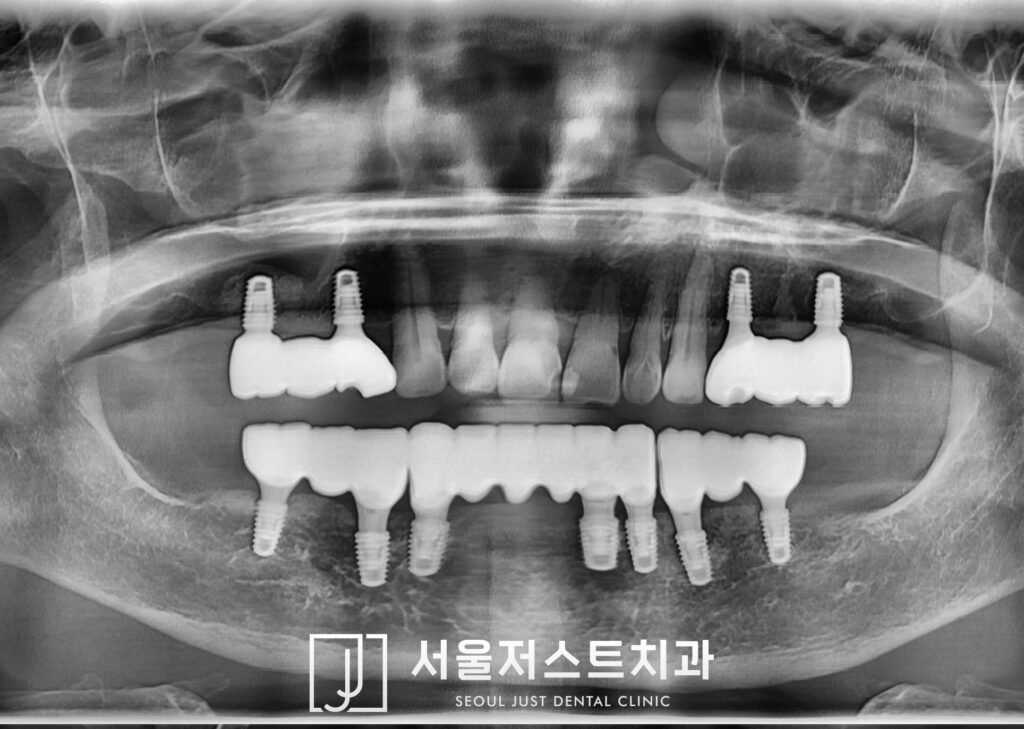

약 2개월 정도 더 기다려준 뒤,

위쪽에도 최종 보철물로 마무리를

하였는데요.